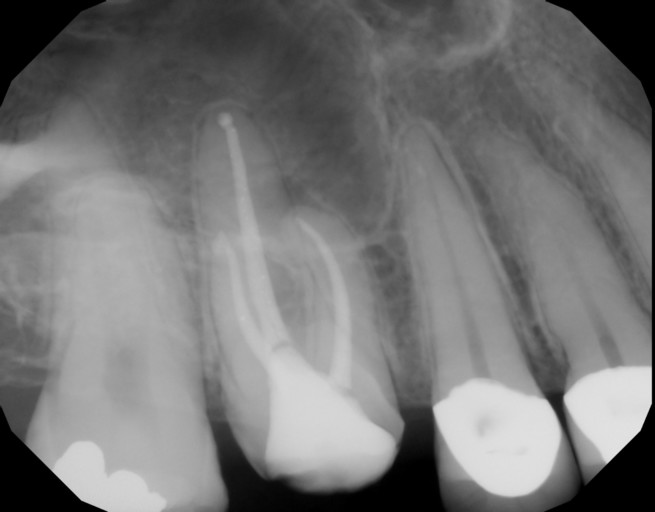

Have had root canal on teeth 8 and 7. still infection and gum boils every few months and pain.

I have had root canals on teeth 8 and 7. This was a two years back on the one tooth and an year and a half on the other about...They want to retreat these teeth, and on the x-ray, the area surrounding these two teeth is black..., I have not really had sensitivity with the teeth before they did the root canals,, the one tooth has a crown, they put it on in a week after the root canal, and that was after I told them I had gotten another gum boil etc. my gum still hurts a lot right before a gum boil forms, and I am afraid that redoing the root canals will not work...what would you suggest? are there better/other options? I really don't have the money, and as it is I have paid over 1k$ on the work that has been done... (I am 18, and just want to do something to make sure it stops...)

Unfortunately, there is no quick fix. When there is an infection present, antibiotics can only treat the symptoms, not the tooth itself. There is a possibility that the teeth can be retreated and will have a favorable long term prognosis. However, with your age and the issues you are having, I would not prepare yourself for a long term restoration. More than likely you will end up losing these teeth at some point in the future. Dental implants are the restoration of choice, especially after a failed root canal. However, they are costly. Dental implants on average are $5000 per tooth from start to finish. It takes from 8-12 months to completely restore a dental implant after the placement and full integration of the bone. To buy time and keep your teeth as long as possible, it may be beneficial to have the teeth retreated if possible, especially with you being so young. This is a large investment financially and emotionally, so several professional opinions may be necessary prior to making a final decision.